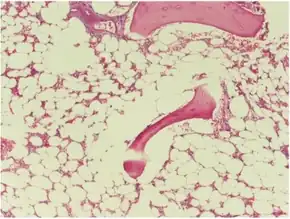

Micrograph of bone marrow taken from a person with aplastic anemia. The bone marrow is mostly fat cells with few blood forming cells.[2]

The cause is unclear in 65% of cases.[3] Other cases may occur following a viral infections, due to a genetic conditions such as Fanconi anemia, or exposure to chemicals, medications or radiation.[3][4] The diagnosis may be suspected based on low blood cells together with low reticulocytes and the absence of changes concerning for blood cancer.[3] The diagnosis is confirmed by a bone marrow biopsy finding mostly fat cells instead of blood forming cells.[5]